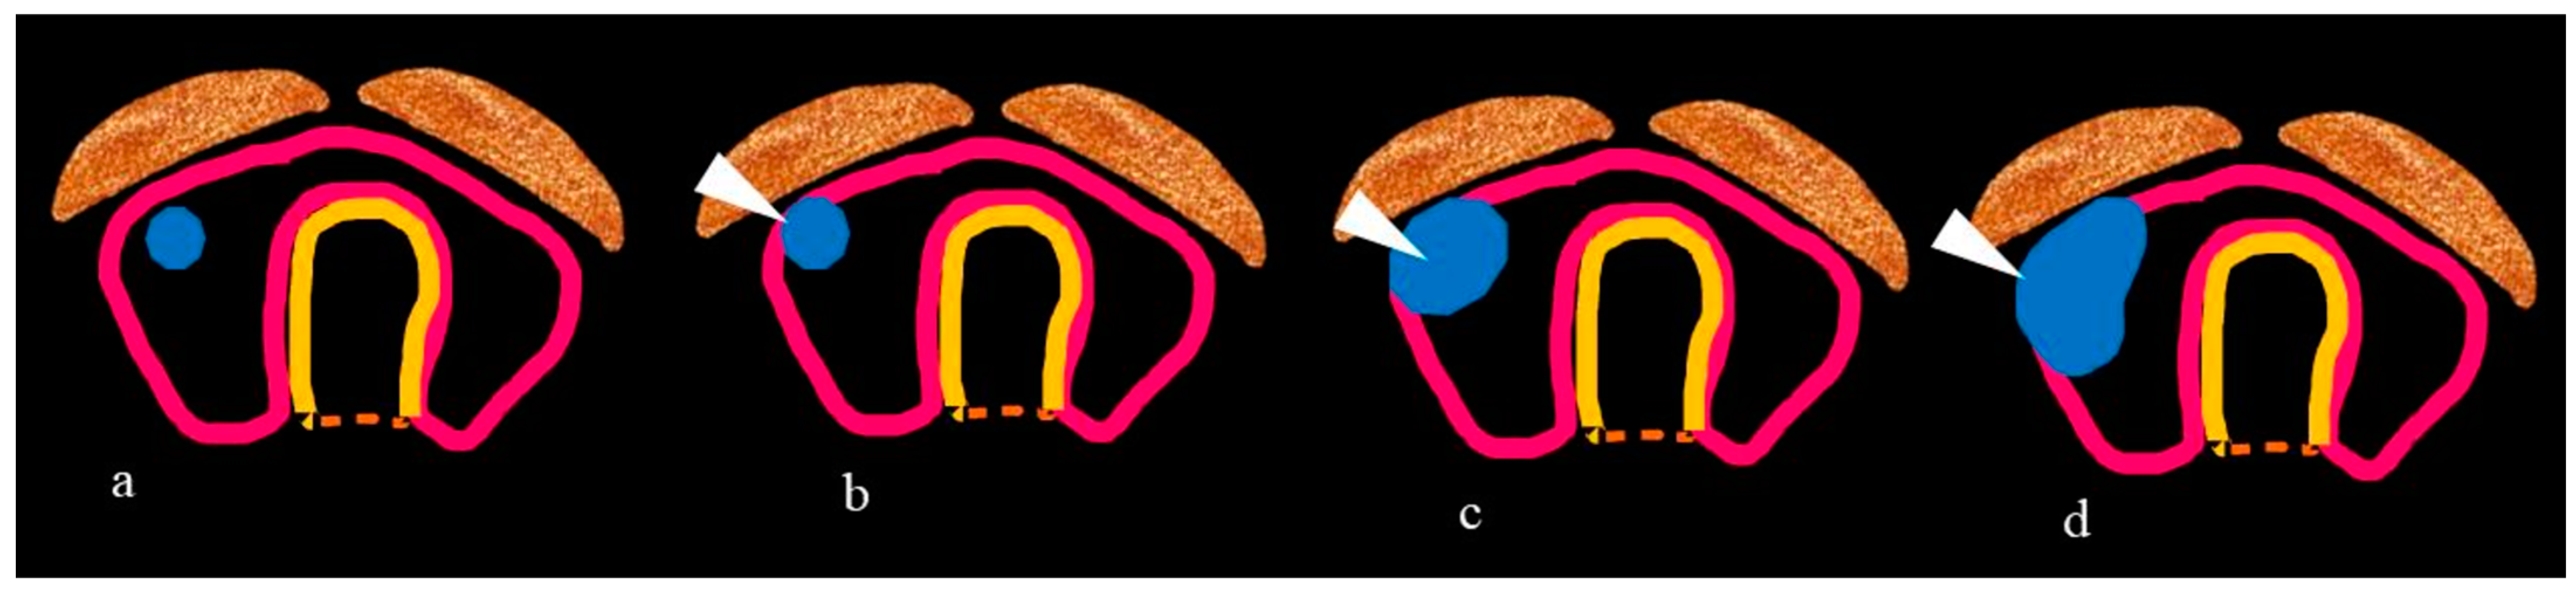

| Tracheal invasion as per SHIN grading (Figure 3) | -Total thyroidectomy with/without RAI -Grade 1: Shave procedure without any residual disease -Remaining grades: window resection/circumferential tracheal resection and re-anastomosis. |

- Mahajan, A.; Sable, N.; Vaish, R.; Chaukar, D.; Chaturvedi, P.; Pai, P. CT based modified SHIN classification for grading trachea Invasion: Addressing the resectability issues in Thyroid cancer. In Proceedings of the European Congress of Radiology-ECR 2019, Vienna, Austria, 27 February–3 March 2019. [Google Scholar]